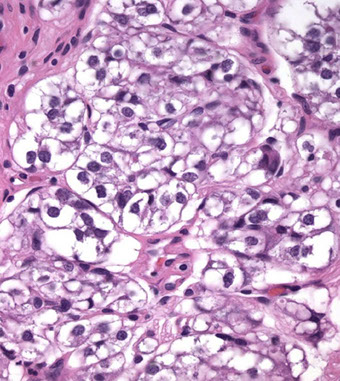

Carcinomas Mimicking B9 Glands

Some ca can closely resemble b9 glands in architecture or cytology and may not be seen as malig

- IHC may be needed to confirm lack of basal cells

Foamy glands ca can be seen c abundant foamy cytoplasm, c gland crowding or infiltrative glands, usually c pink acellular intraluminal secretions

- though cytoplasm can appear xanthomatous, it does  not contain lipid, but empty vacuoles

- nuclear enlargement and prominent nucleoli usually absent

- nuclei are usually small, round and hyperchromatic

- foamy gland ca usually admixed c regular prostatic AC

- can have prominent desmoplastic stromal rxn, which can obscure the ca

- occasional cells may aberrantly express HMWK in non-basal cells

Foamy gland AC